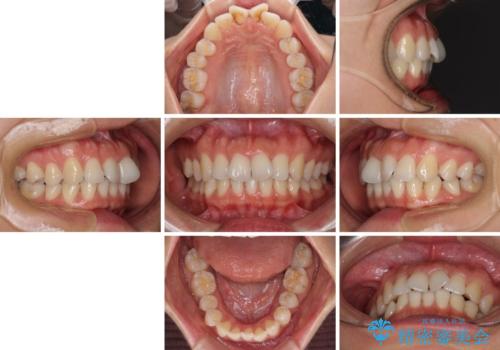

- 捻れた前歯が飛び出しており、口が閉じにくいとのことで来院された患者様です。

出っ歯というわけではないものの、前歯の捻転により口唇が押し出されている状態でした。

親知らずを抜去し、歯列全体を後方に移動させつつ、IPR(歯と歯の間を削る)でスペースを獲得し、インビザラインを用いて叢生を解消しながら前歯の突出を改善することとしました。

骨格的に上下正中がずれていたため、奥歯がしっかりと噛み合うか心配でしたが、ずれているなりに、しっかりとした咬み合わせとなりました。